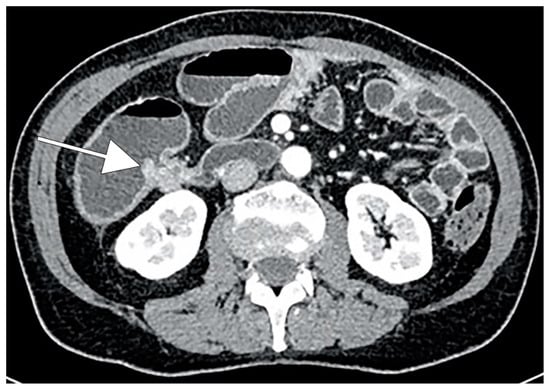

- Minordi, L.M.; Binda, C.; Scaldaferri, F.; Holleran, G.; LaRosa, L.; Belmonte, G.; Gasbarrini, A.; Colosimo, C.; Manfredi, R. Primary neoplasms of the small bowel at CT: A pictorial essay for the clinician. Eur. Rev. Med. Pharmacol. Sci. 2018, 22, 598–608. [Google Scholar] [PubMed]